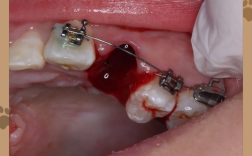

- 创口裂开:可见牙龈瓣分离,牙槽骨暴露(暴露面积从1-5mm不等),严重时可见牙槽窝内血凝块脱落或肉芽组织增生。

(二)中度裂开(2-5mm,骨暴露但无坏死,无感染)

- 重新缝合:在局麻下拆除原缝合线,彻底清创(去除血凝块、肉芽组织),采用“减张缝合+褥式缝合”联合方法:先在创口两侧牙龈做水平松弛切口,减少张力,再用褥式缝合将牙龈瓣固定于骨面,确保无死腔。

- 生物膜覆盖:对于骨暴露区域,可覆盖胶原膜或可吸收生物膜,引导骨组织再生,同时保护创口。